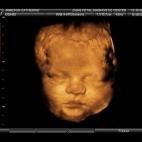

En esta galería puedes ver en fotos como es el desarrollo de un feto de semana en semana:

Desarrollo del feto, en fotos